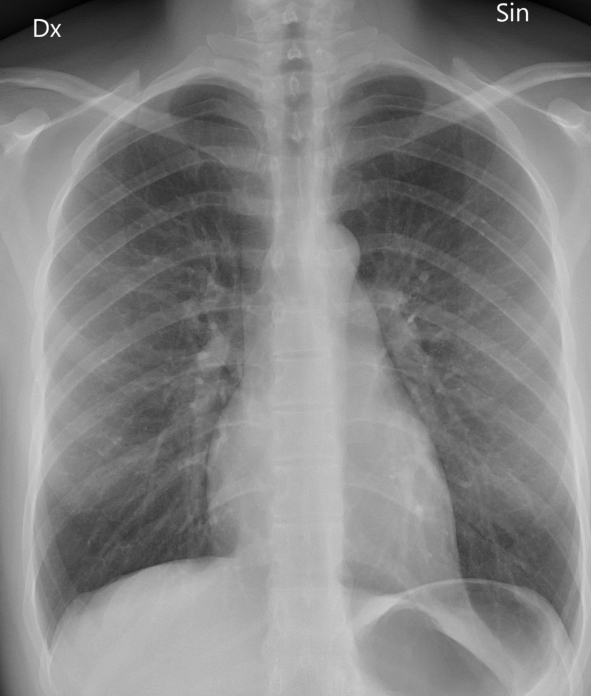

엑스레이는 가볍고 빠른 검사예요. 병원에서 기침이나 흉통이 있으면 가장 먼저 찍는 사진이죠. 하지만 엑스레이는 가슴 속 장기를 한 번에 찍기 때문에, 여러 구조가 겹쳐 보입니다. 그만큼 정확한 구분이 어렵고, 미세한 결절이나 염증은 지나치기 쉽습니다.

흉부CT는 이야기가 달라요. 얇게 자른 단면을 수백 장 촬영하기 때문에, 작은 병변도 놓치지 않습니다. 마치 산 전체를 한 장의 사진으로 보는 엑스레이와 달리, CT는 나무 한 그루 한 그루를 자세히 보는 느낌이에요. 예전에 병원에서 일했던 친구 말로는, 엑스레이에 아무 이상이 없던 환자가 CT에서 폐암 초기 진단을 받은 경우도 많았다고 합니다. 그만큼 CT는 정밀한 탐색 도구입니다.

흉부ct로 볼수있는 질환 폐질환뿐 아니라 심장과 혈관, 흉막, 림프절, 뼈 구조까지 한 번에 보여줍니다. 폐렴, 결핵, 폐기종, 기관지확장증, 간질성 폐질환 같은 호흡기 질환은 기본이고, 폐에 생긴 작은 결절이나 혹도 세밀하게 확인할 수 있습니다. 폐암이나 전이암처럼 초기에 증상이 거의 없는 병은 CT로 발견되는 경우가 많아요.

또한 폐렴이 감염인지, 결핵성인지, 종양에 의한 것인지도 구분할 수 있습니다. 엑스레이에서는 그냥 ‘흐린 그림자’로만 보이던 것도, CT에서는 염증의 경계와 내부 구조까지 뚜렷하게 드러납니다.